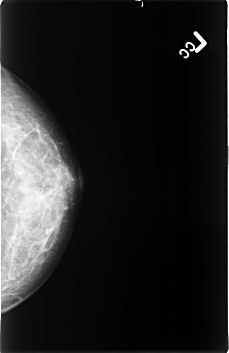

B_3403_1.LEFT_MLO

B_3403_1.LEFT_CC

LEFT_MLO LINES 4496 PIXELS_PER_LINE 2968 BITS_PER_PIXEL 12 RESOLUTION 50 NON_OVERLAY